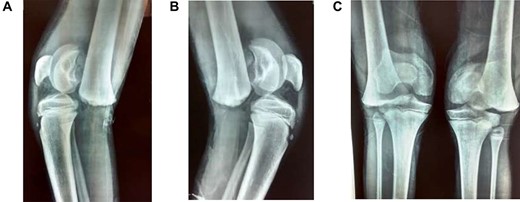

A 9-year-old male presented to the ER within 6 h of injury to both knees, with swelling, restricted movements and tenderness bilaterally. Assessment demonstrated distal pulses in both legs. Initial management was with pain relief—neurological status was not assessed due to pain. A history of direct fall of a concrete block onto both knees whilst sitting with legs extended and raised on a stool at a building site, leading to a forced hyperextension injury, was elicited. The patient received no treatment before presenting to our unit. Radiography suggested bilateral completely displaced Salter-Harris Type I fractures (Fig 1A–C). All routine laboratory and metabolic profiles performed were within normal ranges. Patient was transferred to theatre immediately after radiography for a closed reduction.

(A) Lateral view of right knee at presentation, (B) lateral view of left knee at presentation, (C) frontal view of both knees at presentation